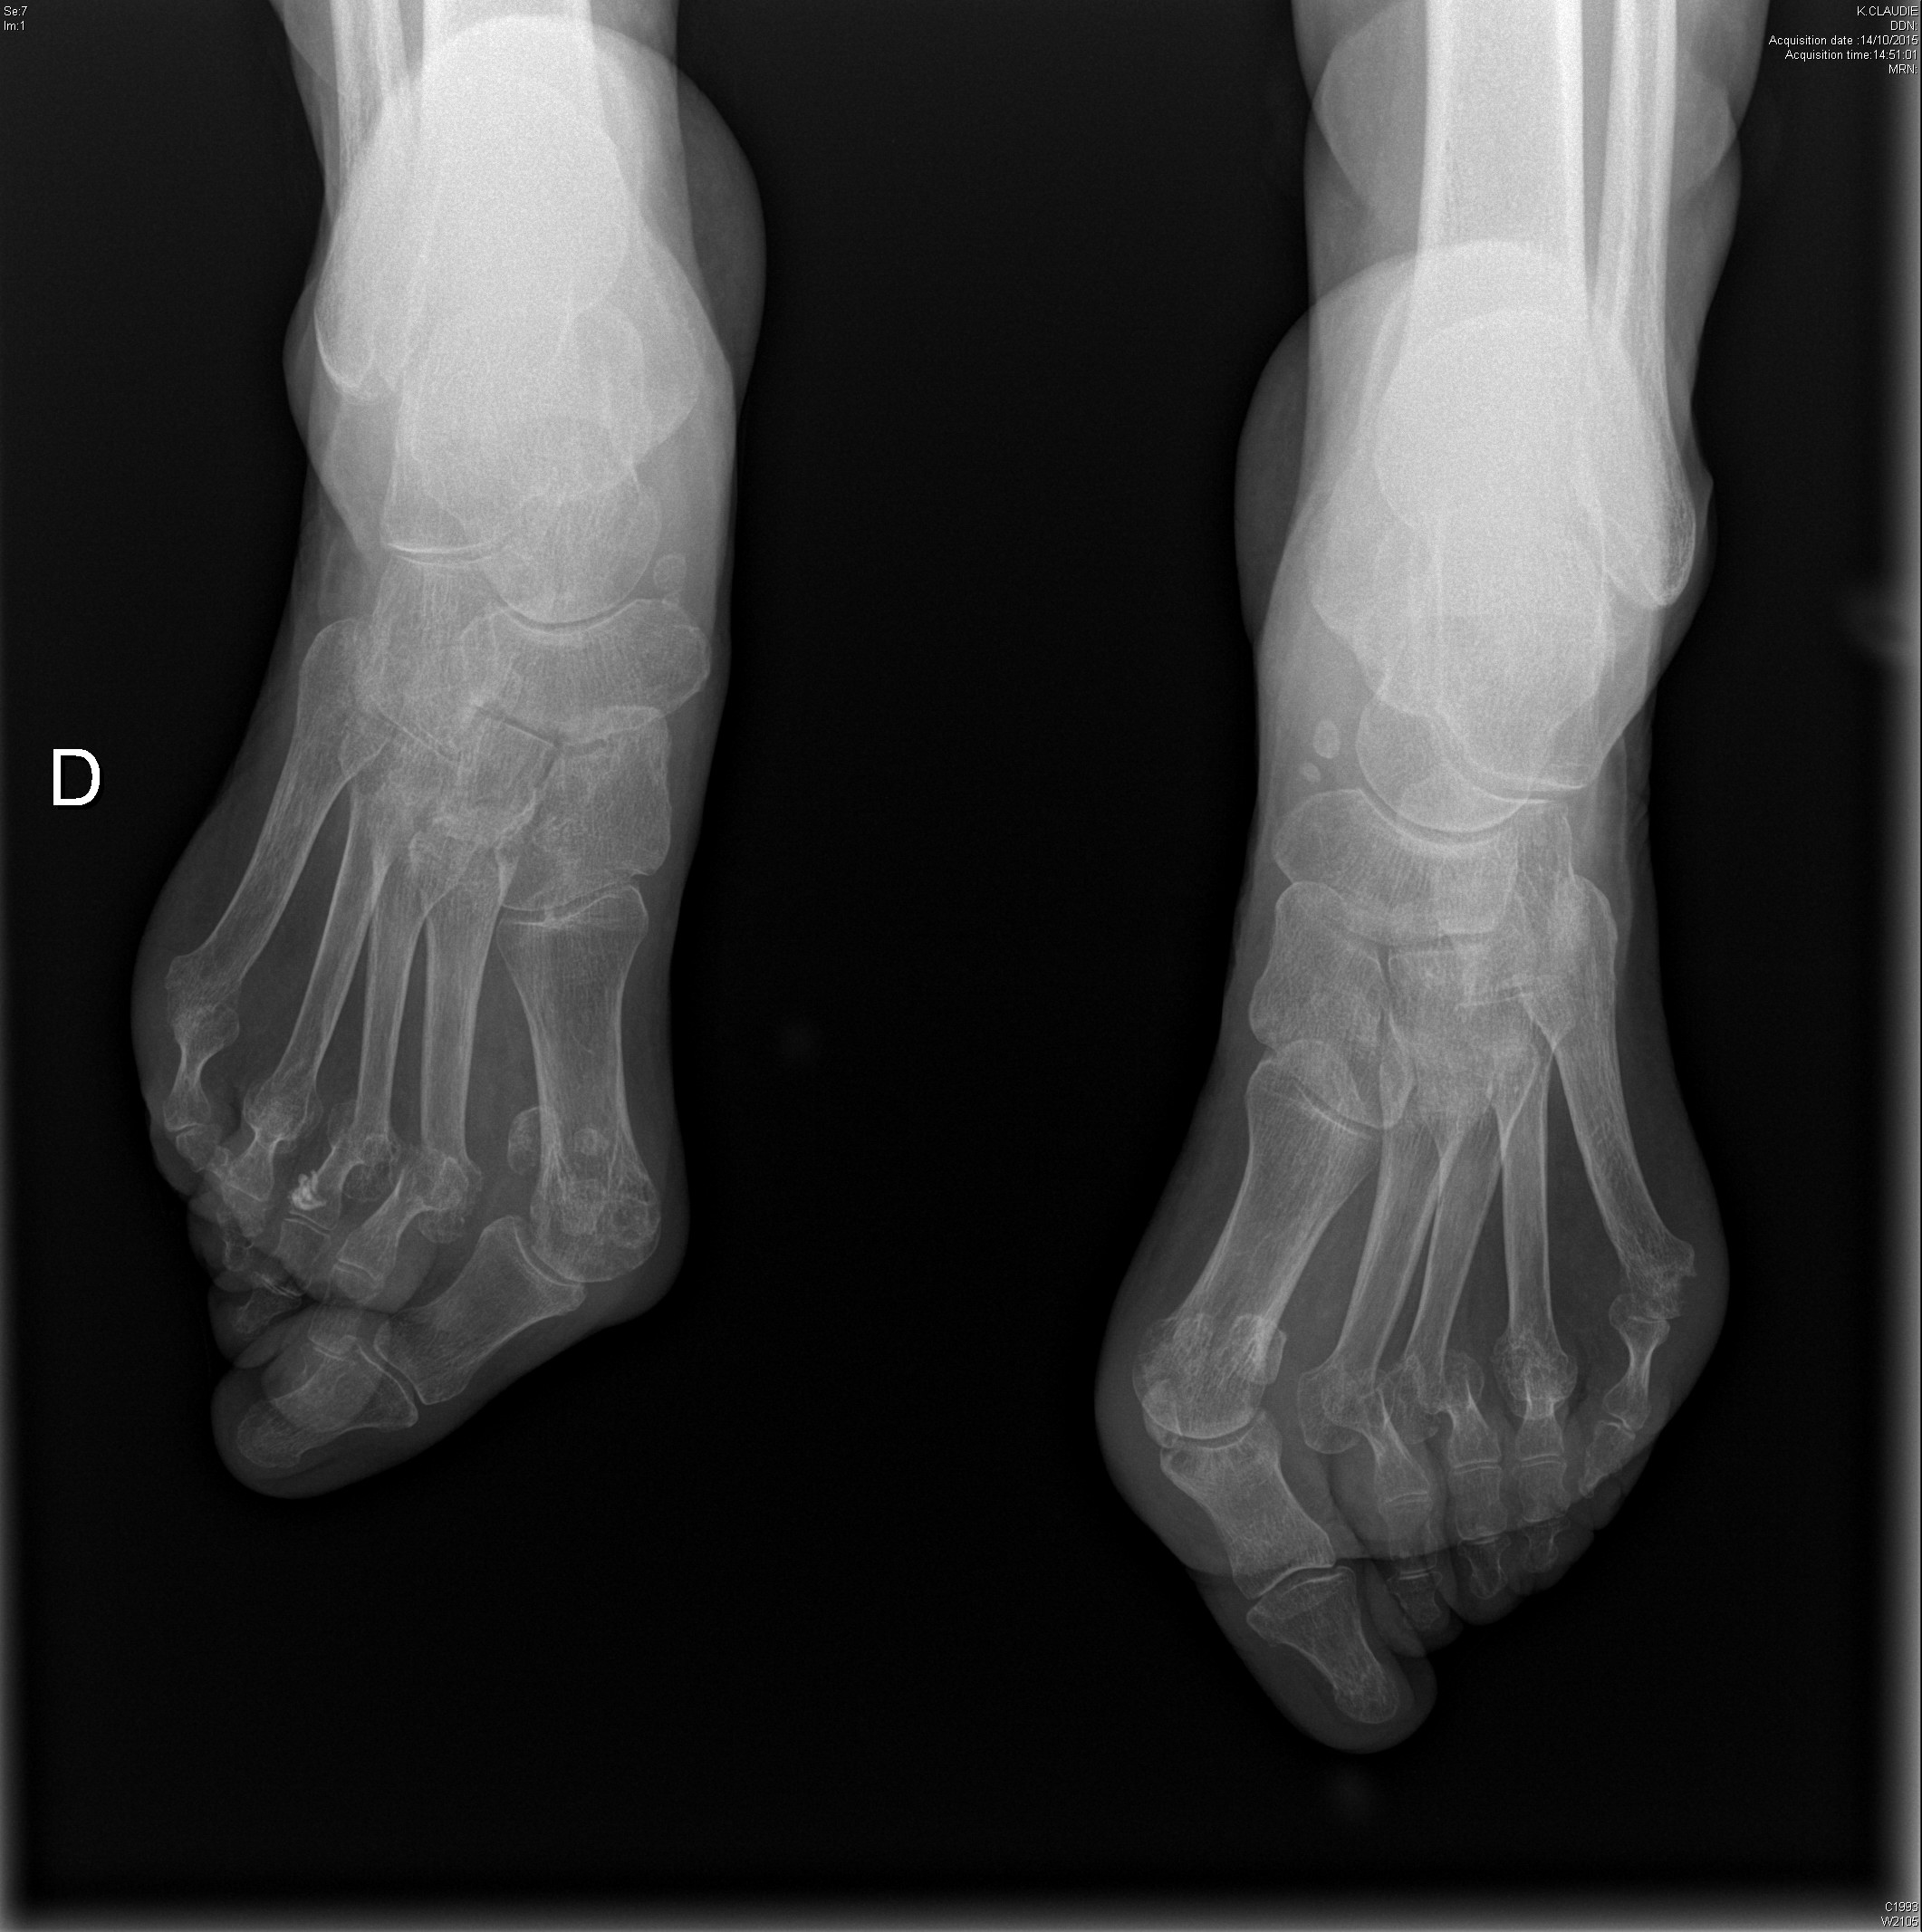

Radiographie retrouvant une dysplasie acétabulaire bilatérale ainsi qu'une lésion de dysplasie fibreuse du col fémoral droit chez une jeune fille